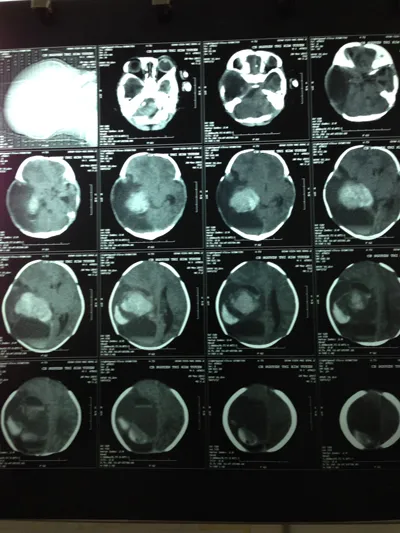

Hình chụp trước mổ thấy khối u não (màu trắng) trong não bệnh nhi.

Kết quả chụp CT não bệnh nhi thấy có một khối u não lớn bên phải có biểu hiện chảy máu trong khối u. Một tuần sau bệnh nhi tiếp tục được chụp MRI, các BS nghi ngờ u quái khổng lồ với kích thước 6 x 8 cm, tính luôn phần máu tụ do u não vỡ chảy ra là 10x15 cm.